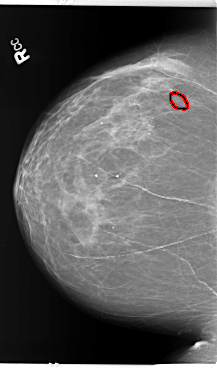

B_3141_1.RIGHT_MLO

RIGHT_MLO LINES 5936 PIXELS_PER_LINE 3848 BITS_PER_PIXEL 12 RESOLUTION 50 OVERLAY

FILE: B_3141_1.RIGHT_MLO.OVERLAY

TOTAL_ABNORMALITIES 1

ABNORMALITY 1

LESION_TYPE CALCIFICATION TYPE PLEOMORPHIC DISTRIBUTION CLUSTERED

ASSESSMENT 4

SUBTLETY 3

PATHOLOGY BENIGN

TOTAL_OUTLINES 1

BOUNDARY